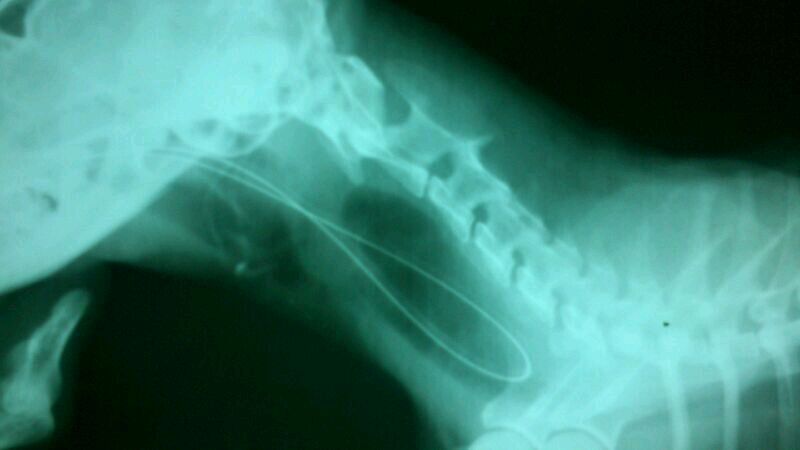

預計鼻胃管餵插管,插管後的x光檢查後發現鼻胃管無法進入食道

轉診其他醫院確診沾黏,建議安樂死